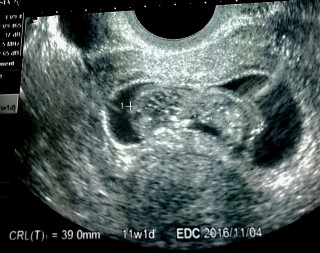

左が頭CRL39mm。4日分大きめの計測。動いている姿を見られました。 前回の受診は8日前の9w3dで23mmでした。10w、30mmの壁は越えられました。次なる目標は16w。